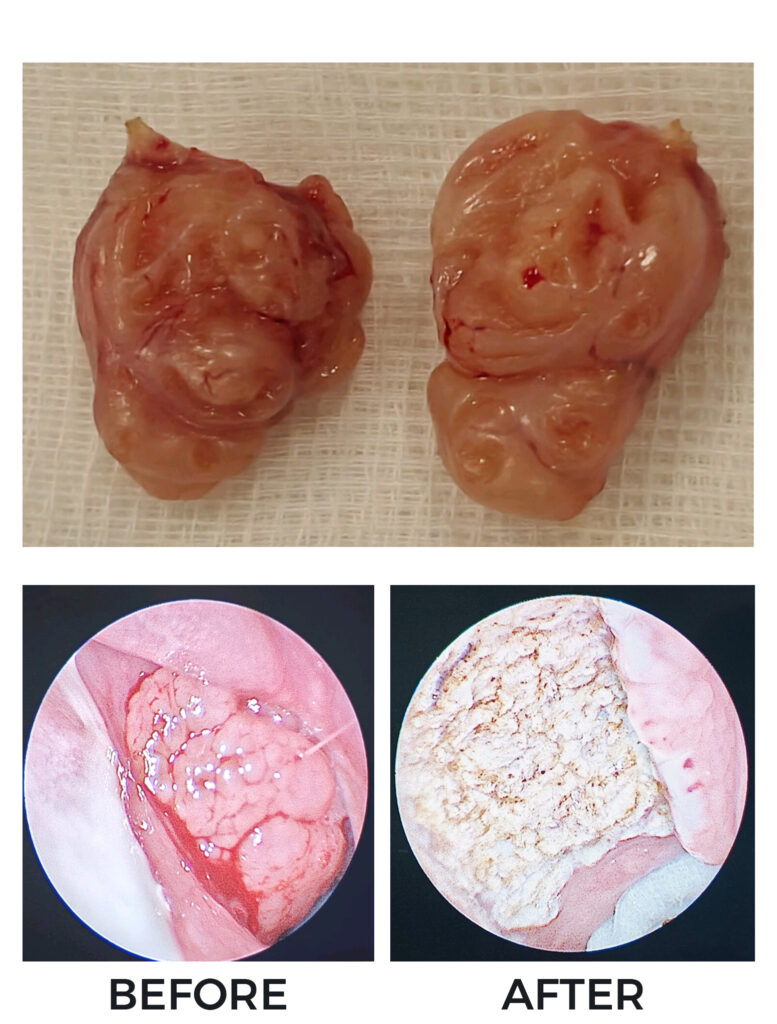

Adenotonsillectomy

Endoscopic Coblation Adenoidectomy

Medtronic BiZact assisted bloodless Tonsillectomy